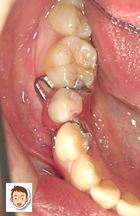

10代の女性。主訴は「乳歯が抜けたまま大人の歯が生えてこない」でした。レントゲンで確認すると、永久歯の本数が1本少ない事が分かりました。このまま放置されると、歯が傾きだして、歯並びにも影響します。そこで「脱着式の部分入れ歯」を入れて、「歯並びをKeep」することを提案しました。

型取りをしてから4日後、試作の入れ歯が届きました。

チェックポイントは

①カタカタせずに、ぴたっと入るか?

②痛い所はないか? 噛み合わせは大丈夫?

③デザインは優れているか?(他人から見て、入れ歯と分からないような設計になっているか?)

など細かくみます。 続きを読む